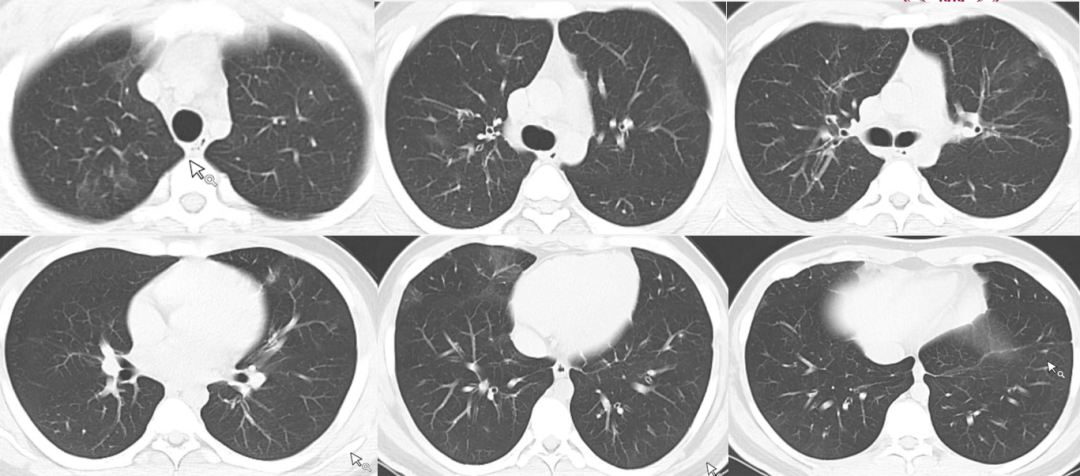

2023年11月20日胸部CT显示窦道形成,2024年1月14日胸部CT可见恢复较好,病变基本吸收(图13)

图片

图13  患者胸部CT

三、相似病例

病例1,男性,42岁,浙江衢州务工,油漆工,既往体健。发热半月,伴全身酸痛,咽痛,体温39℃,咳嗽,咳黄痰,当地医院拟“肺炎”住院,予抗感染治疗后无好转,转至我院,拟“社区获得性肺炎”于2023年4月7日收住。甲型流感合并气管支气管曲霉病。

病例1胸部CT

病例1气管镜检查

病例2,女性,39岁,肾移植术后7个月。因“发热1周、呼吸费力伴声音嘶哑2天”于2024年1月14日入院。最终诊断为乙型流感合并气管支气管曲霉病。

病例2胸部CT

病例2气管镜检查